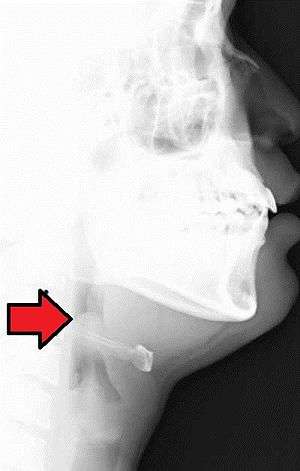

| Neck X-ray showing thumbprint sign. | |

Epiglottitis was historically mostly caused by infection by H. influenzae type b.[2] With vaccination it is now more often caused by other bacteria.[2] Other possible causes include burns and trauma to the area.[2] The most accurate way to make the diagnosis is to look directly at the epiglottis.[4] X-rays of the neck from the side may show a "thumbprint sign" but the lack of this sign does not mean the condition is absent.[2]

On lateral C-spine X-ray, the thumbprint sign describes a swollen, enlarged epiglottis;[13] usually with dilated hypopharynx and normal subglottic structures.